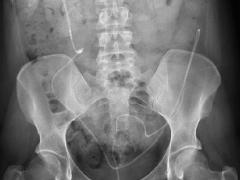

Een zwangere met acute buikpijn

Casuïstiek

Besluitvorming bij kwetsbare patiënt met heupfractuur